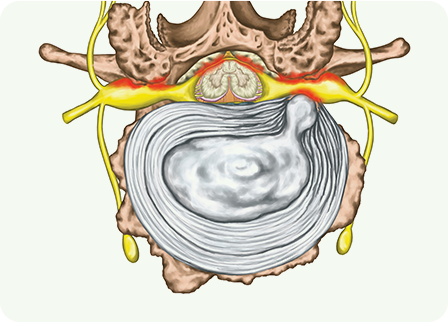

목디스크(추간판 탈출증)는 척추 사이에서 완충 역할을 하는

디스크가 손상되어 돌출하거나 신경을 압박하는 상태

입니다.

디스크는 퇴행성 변화, 과도한 압력, 잘못된 자세, 외상 등으로 인해

약화되고 섬유륜에 균열이 생겨 수핵이 탈출할 수 있습니다.

이로 인해 목 통증, 팔 저림, 감각 이상 및 근력 약화 등의

증상이 나타납니다.